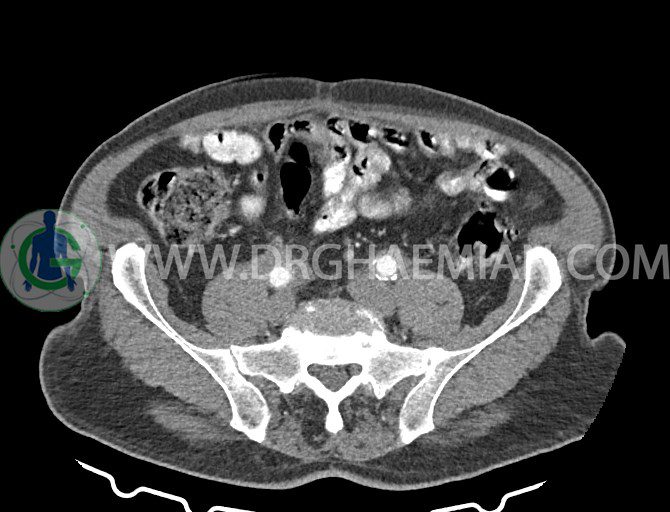

سی تی اسکن لگن یکی از روش های تصویربرداری با سی تی اسکن است. این روش با استفاده از تشعشعات تصاویر عرضی از ناحیه شکمی ایجاد میکند. در این کیس ديورتيكولوزيس، کیست های کورتیکال در هر دو کلیه، لنفادنوپاتی، کلسیفیکاسیون دیواره آئورت و شریان ایلیاک، تغییرات DJD ناحیه توراکولومبار و پروستات بزرگتر از عادی دیده می شود.

در سي تي اسکن اسپيرال شکم و لگن با و بدون کنتراست خوراکی و وريدی (مولتي ديدکتور 16 با مقاطع ظريف و بازسازي هاي ساژيتال و کرونال):

– کيست هاي کورتيکال ساده به قطر 5 mm تا 50 mm در کليه راست و به قطر 5mm تا 55 mm در کليه چپ

– توده ايزودنس به ابعاد mm 17 x 28 در پره ائورت مجاور قسمت تحتاني D3 دئودنوم مطرح کننده لنفادنوپاتي و با احتمال کمتر آنوريسم ترومبوزه (نيازمند مطابقت سونولوژيک)

– ديورتيكولوزيس در کولون نزولي وسيگموئيد

لنفادنوپاتي به ابعاد mm 22 x 25 مجاور شريان ايلياک خارجي چپ و به ابعاد mm 17 x 28 مجاور شريان ايلياک خارجي راست